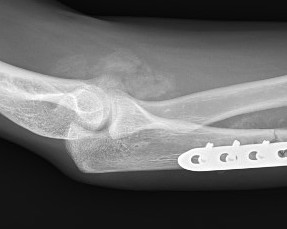

Elbow HOElbow HO Excision Post op

+/- hinged external fixator

Elbow Post HO Excision